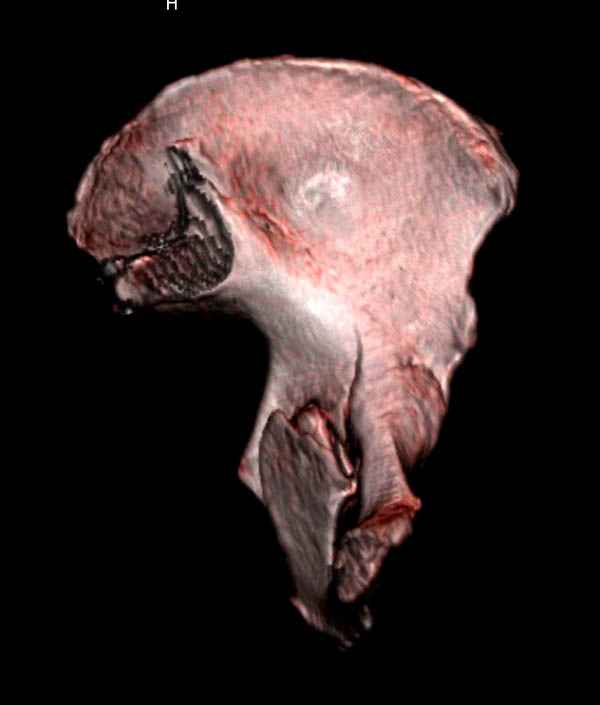

Имя     : 12 acetabulum fem neck 3D.jpg

Тип     : image/jpeg

Размер  : 23128 байтов

Описание: отсутствует

Url     : http://weborto.net:8080/pipermail/ortho/attachments/20080116/651190cc/attachment-0012.jpg

Имя     : 14 acetabulum fem neck 3D.jpg

Размер  : 27750 байтов

Url     : http://weborto.net:8080/pipermail/ortho/attachments/20080116/651190cc/attachment-0013.jpg

Имя     : 15 acetabulum fem neck 3D.jpg

Размер  : 24795 байтов

Url     : http://weborto.net:8080/pipermail/ortho/attachments/20080116/651190cc/attachment-0014.jpg